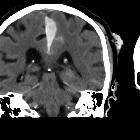

Subdural

hemorrhage • Falx subdural hematoma and sulcal subarachnoid hemorrhage - Ganzer Fall bei Radiopaedia

Parafalzines

Subduralhämatom mit zusätzlicher Subarachnoidalblutung beidseits nach Sturz.